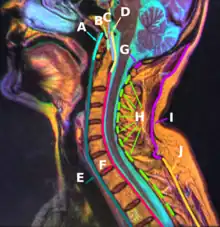

E:Anterior longitudinal ligament

Median sagittal section through the occipital bone and first three cervical vertebræ.